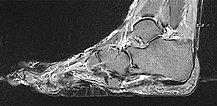

The cerebriform mixed connective tissue nevus is also homogeneously hypointense (black) on sagittal non-enhanced, T1-weighted MRI (same plane).

Sagittal , T1-weighted, fat-suppressed MRI (again, the same plane) shows slight, relatively homogeneous contrast enhancement of the nevus.